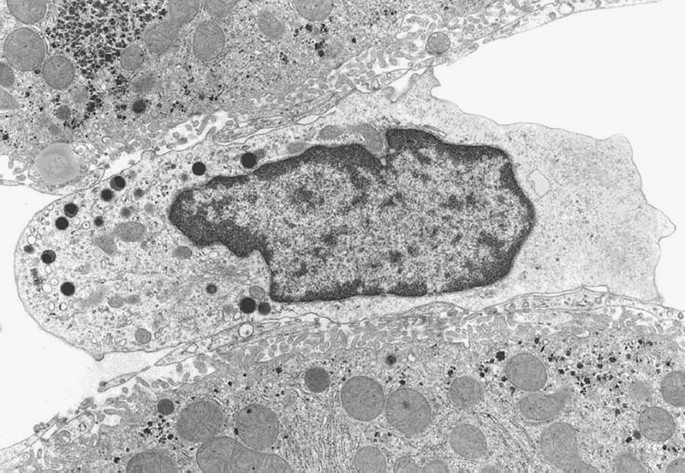

Pit cells have a diameter between those of lymphocytes and granulocytes. Similar to Kupffer cells, the shape of pit cells is irregular and variable (Figure 1). Pit cells are attached to the endothelial lining, which they might penetrate with little microvilli ‘shaking hands’ with the microvilli of parenchymal cells, as if they are anchoring or securing their position. Pit cells are not located in the space of Disse. These cells are often neighbors of Kupffer cells and even make contact with Kupffer cells, suggesting some type of physical relationship. Most remarkable are the numerous, characteristic granules (Ø 0.3 μm) that lie together in one part of the cytoplasm (Figure 2). These granules are round and have an electron-dense content with an even darker characteristic dense core. This content is surrounded by an electron-lucent halo and a single membrane. The other part of the cytoplasm is hyaloplasmic or contains only a few small organelles, such as single strands of rough endoplasmic reticulum, a small Golgi apparatus, free ribosomes, and few small mitochondria. Kaneda et al.44 described an additional type of granule for pit cells: the so-called ‘rod cored vesicle.’ These granules are smaller, less frequent, and electron-lucent with a central rod, and they are not comparable to the typical pit cell granules. We also found pit cells with fewer and larger granules in the peripheral blood and the spleen. It was easy to find pit cells in the livers of other species (dogs, mice, and hamsters), except for human liver. Unlike Kupffer cells, pit cells do not possess a phagocytic or endocytic function. Pit cells were unreactive in many experimental conditions, except for partial hepatectomy, in which we found pit cell mitosis in the remaining part of the liver.42

Figure 1

Pit cell in a normal rat liver (Wistar). Organelles are situated on one side of the central nucleus. The other side of the cell is composed of hyaloplasm without organelles. The pit cell makes contact with sinusoidal endothelial cells, and microvilli sometimes protrude into the space of Disse (top left). Pit cells possess characteristic electron-dense granules, in addition to a small number of mitochondria, RER cisternae, and a Golgi apparatus. The pit cell in this figure measures approximately 8 μm in length.